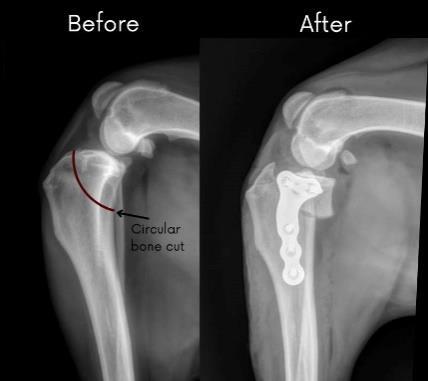

A TPLO consists of making a moon shaped cut in the tibia, and then rotating the upper segment until the

angle between the tibia and femur is approximately level. This can range between 2-14 degrees, with 5 degrees being the angle most vets aim for. A metal plate will then be screwed onto the 2 sections of tibia, holding them in place, and allowing them to heal into their new shape.

Before and after X-rays of a TPLO.